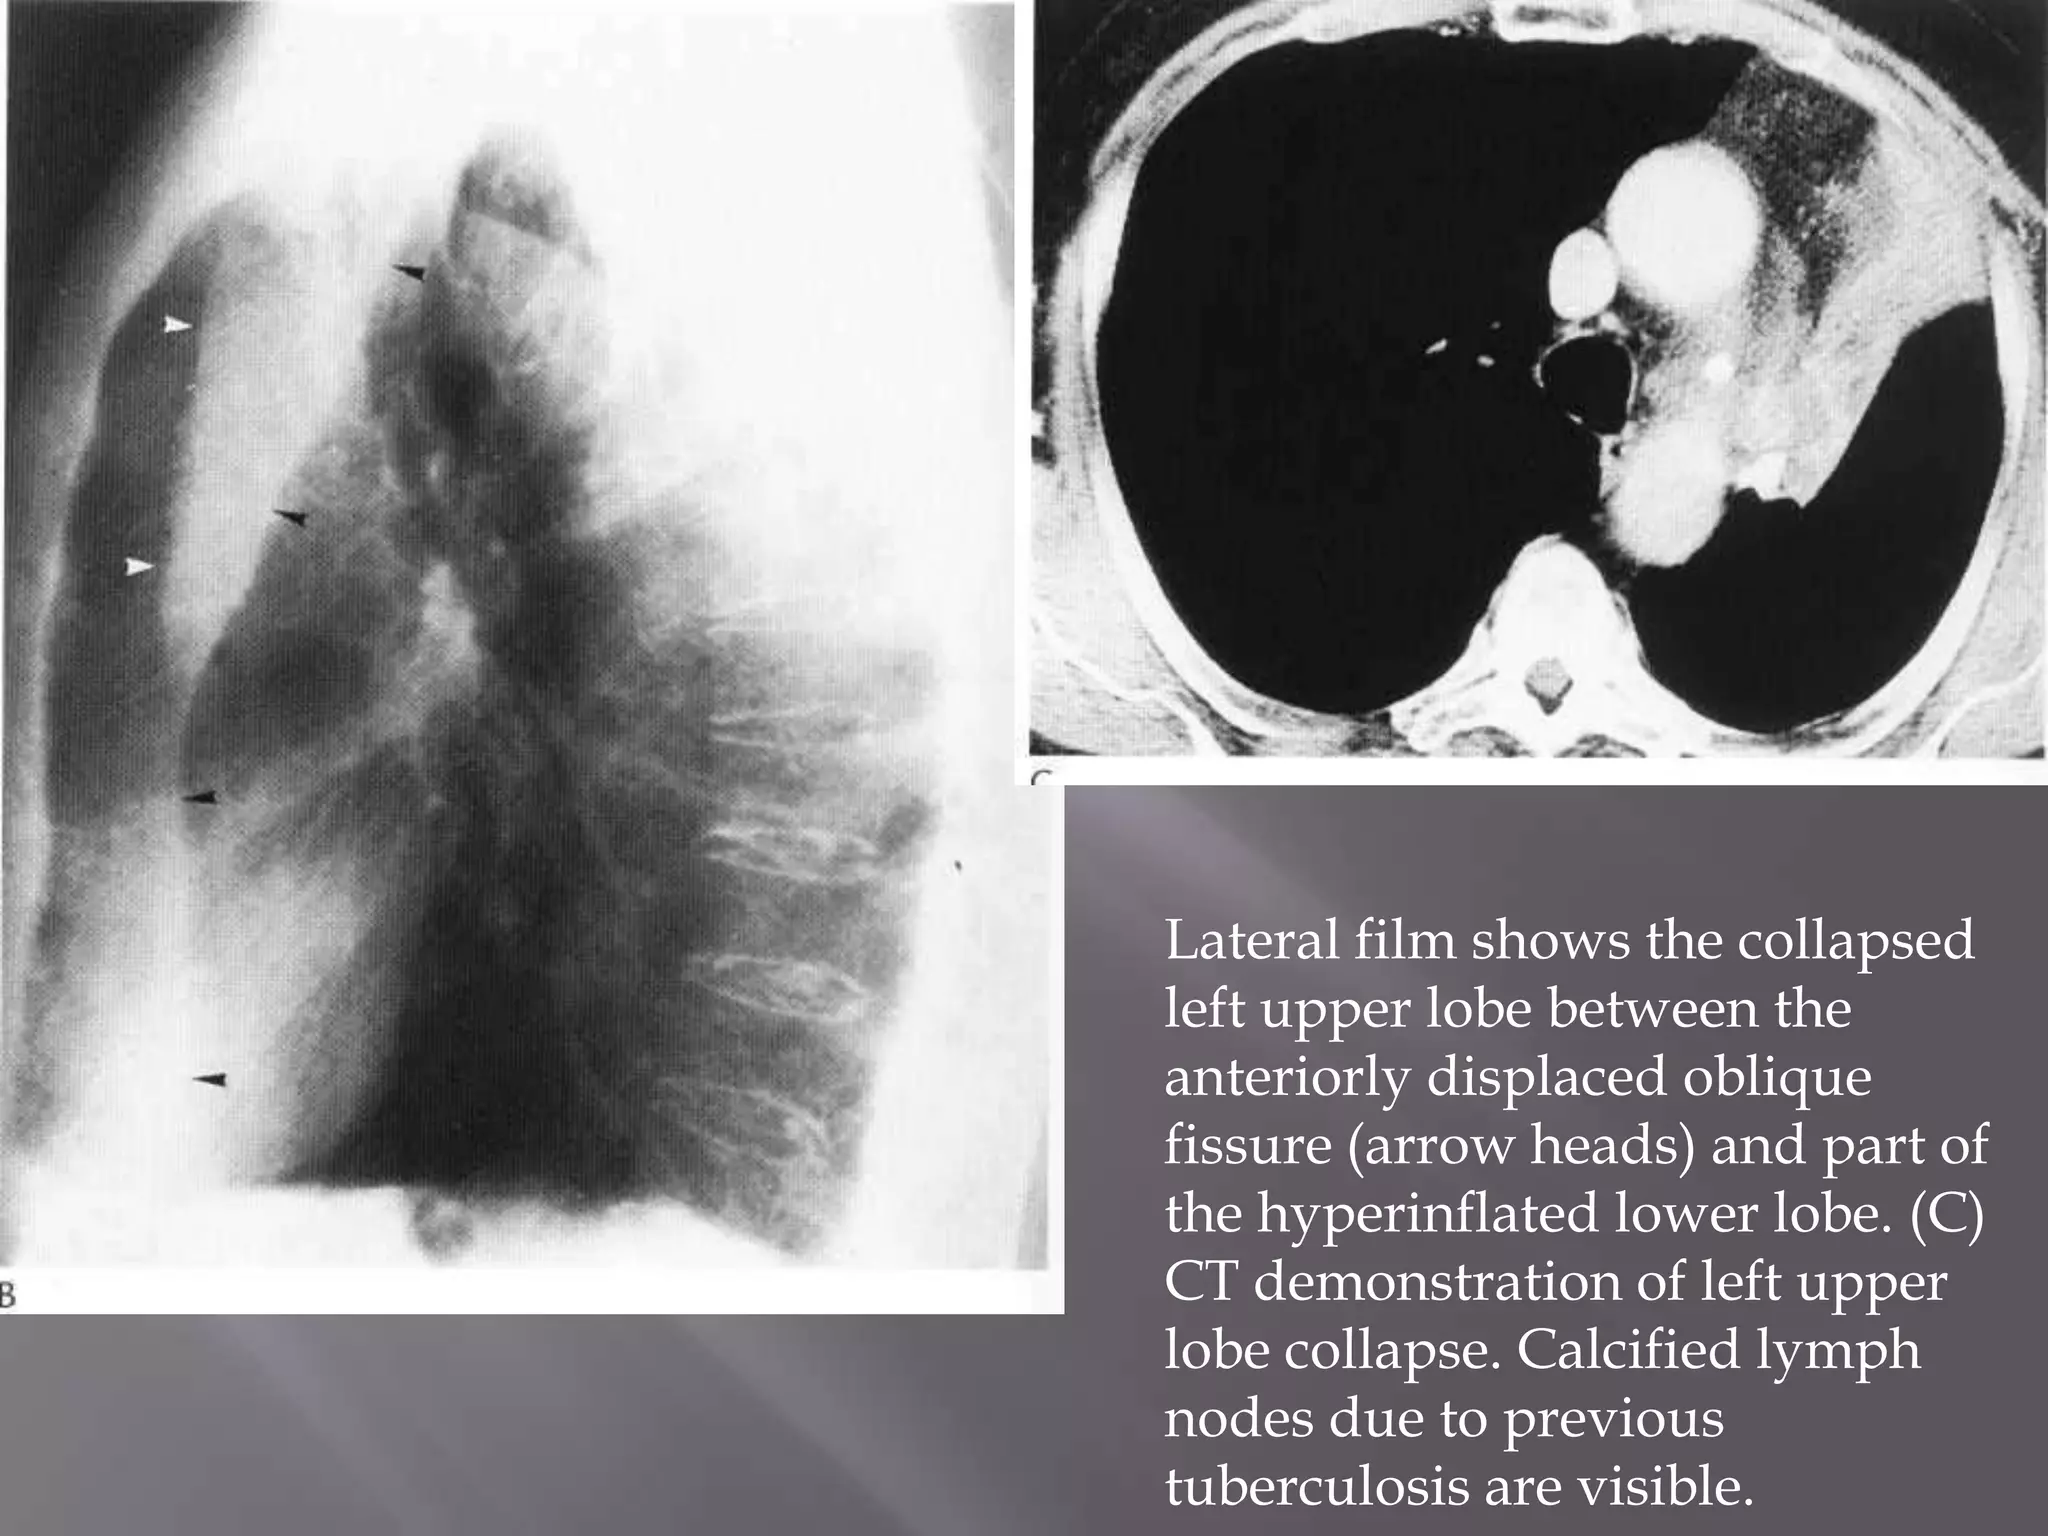

Lateral film shows the collapsed

left upper lobe between the

anteriorly displaced oblique

fissure (arrow heads) and part of

the hyperinflated lower lobe. (C)

CT demonstration of left upper

lobe collapse. Calcified lymph

nodes due to previous

tuberculosis are visible.

Lateral film showsthe collapsed left upper lobe between the anteriorly displaced oblique fissure (arrow heads) and part of the hyperinflated lower lobe. (C) CT demonstration of left upper lobe collapse. Calcified lymph nodes due to previous tuberculosis are visible.